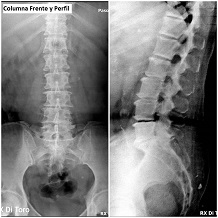

Utilizamos sensores Flat Panel, que nos permiten acortar al Máximo el tiempo de exposición (Dosis de Radiación) y obtener la adquisición inmediata de las imágenes.